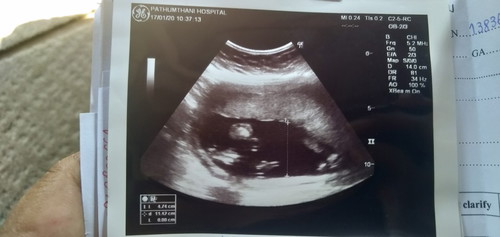

อยากรู้ว่าผู้หญิงหรือชาย

อยากรู้ว่าหญิงหรือชายดูแบบไหนคะ ไปซาวมาหลายครั้งแล้วหมอก็ไม่บอก

กำลังตั้งครรภ์